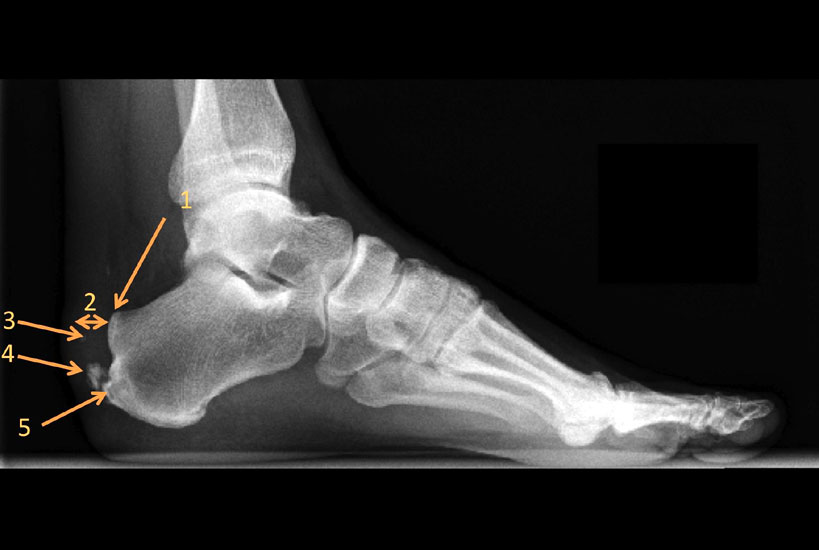

Abbildung 3: Das seitliche belastete Röntgenbild des Fußes zeigt die Pathologien des Achillessehnenansatzes: Retroachilläre Bursitis, die den Karger´schen Fettkörper verdrängt (1), Verdickung der Achillessehne (2), intratendinäse Calcifikationen (3), Trak

Abbildung 3

Außerdem lässt sich auf dem seitlichen Röntgenbild im Bereich der Weichteile häufig als indirektes Zeichen der retroachillären Bursitis eine Aufhellung am Achillessehnenansatz erkennen 11. Des Weiteren ist auf die Ausbildung des retrocalcanearen Recessus und die relative Dicke der Achillessehne zu achten 10. Im Bereich der Achillessehne ist auf einen Traktionsosteophyten, der aus Verknöcherungen im Bereich des Sehnenansatzes durch Mikrotraumatisierungen entsteht  sowie intratendinöse Verkalkungen/-knöcherungen zu achten (Abb. 3).